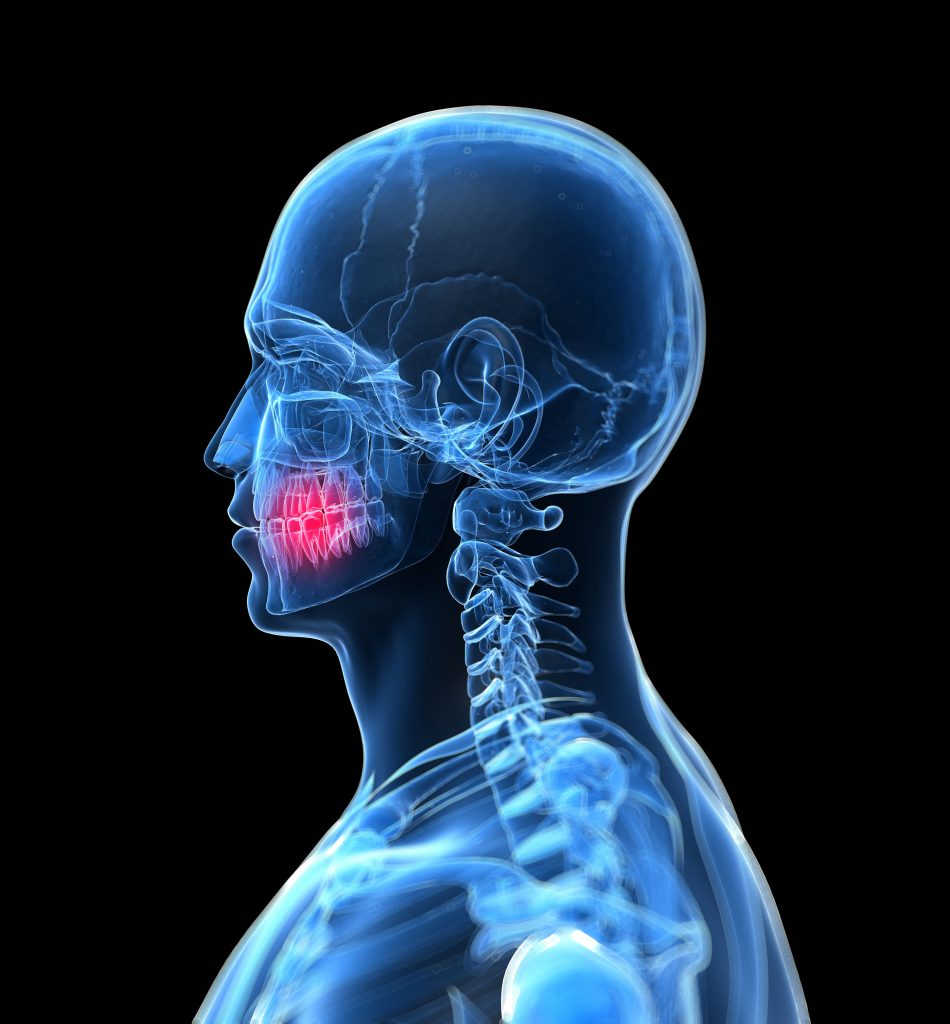

A fogazati betegségek a kezdeti stádiumban nem okoznak panaszt, egy szűrővizsgálaton, egy alapos fogászati diagnosztika során azonban egyszerűen ki lehet mutatni őket. Sajnos sokan hiszik tévesen, hogy csak akkor kell fogorvoshoz fordulni, amikor valamilyen fájdalom jelentkezik a szájüregben. Ezzel ellentétben az igazság az, hogy amikor már fáj a fog, akkor az esetek jelentős részében összetettebb és jóval költségesebb beavatkozásra van szükség.

Minden kezelés alapvető feltétele a pontos diagnózis

Szakorvosaink egyedülálló tapasztalatra tettek szert a fogászati problémák helyes és precíz feltérképezése terén, ami elengedhetetlen a megfelelő kezelési terv összeállításához és végrehajtásához. Munkájukat a legkorszerűbb 3D CBCT készülékek és egyéb fejlett diagnosztikai eszközök támogatják.

Fogorvosi rendelőnkben nagy hangsúlyt fektetünk az alapos fogászati diagnosztikára, a fogakon kívül a csont, az íny, az izmok és ízületek vizsgálatára.